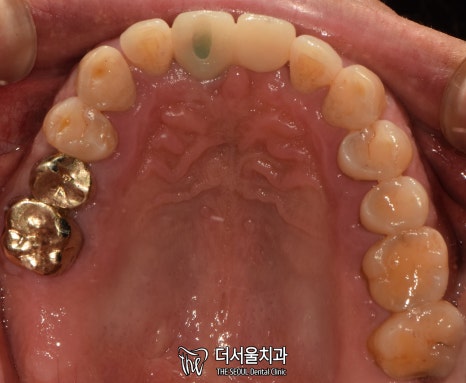

1. 구강 체크

서현역 치과를 찾아오셨던 환자분은

앞니와 왼쪽 끝 어금니에

이상 증세를 느껴 찾아오셨습니다.

겉으로 봤을 때는 큰 문제는 없는 것처럼 보입니다.

그럼 대체 무슨 문제가 있는 걸까요?

겉으로 보여지는 것이 아닌,

속을 들여봐야 알 수 잇겠네요.

엑스레이 촬영을 통해 체크해보겠습니다.